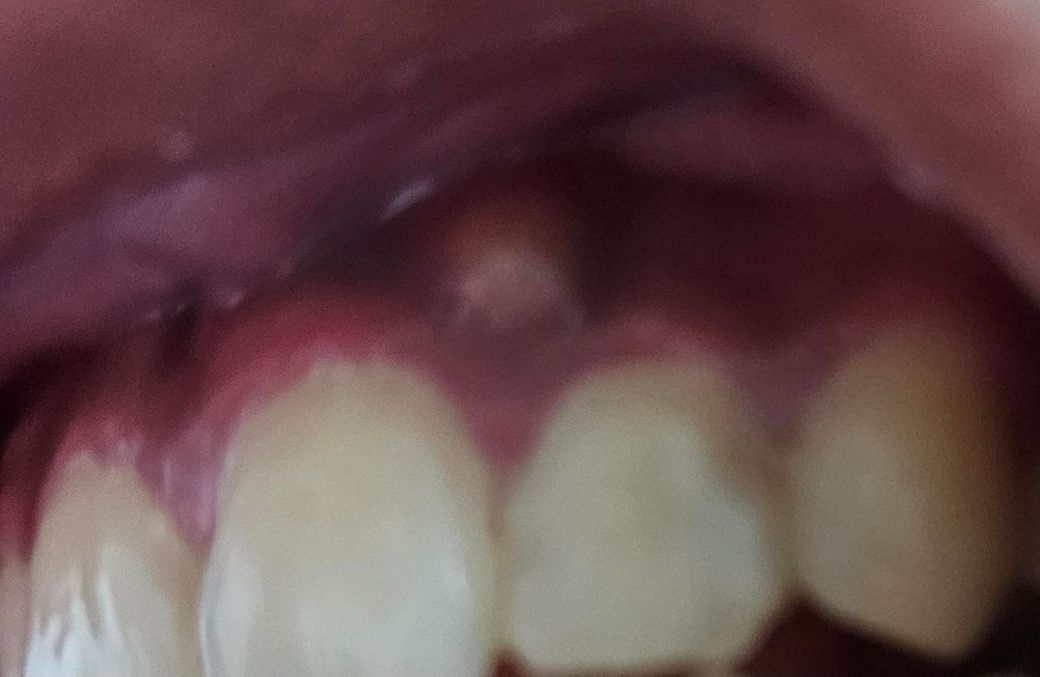

뿌리끝 염증으로 인한 잇몸 누공 답변부탁드려요

근데 지금은 마지막 사진처럼 누공이 생겼습니다 무조건 신경치료를 해야되겠죠..? 누공이 생겼어도 통증이 없으면 안해도 될 가능성이있을까요

• 1번 째 사진

• 2번 째 사진

• 3번 째 사진

엑스레이 상으로는 치아 뿌리끝 염증이 더 확장된거 같습니다. 신경치료를 하시는게 좋을것같습니다.

만성농양의 경우 통증은 없기도 합니다 통증과는 별개로 뼈는 염증때문에 계속 녹고 있는거고요 가급적 신경치료 빨리 받으면 좋습니다